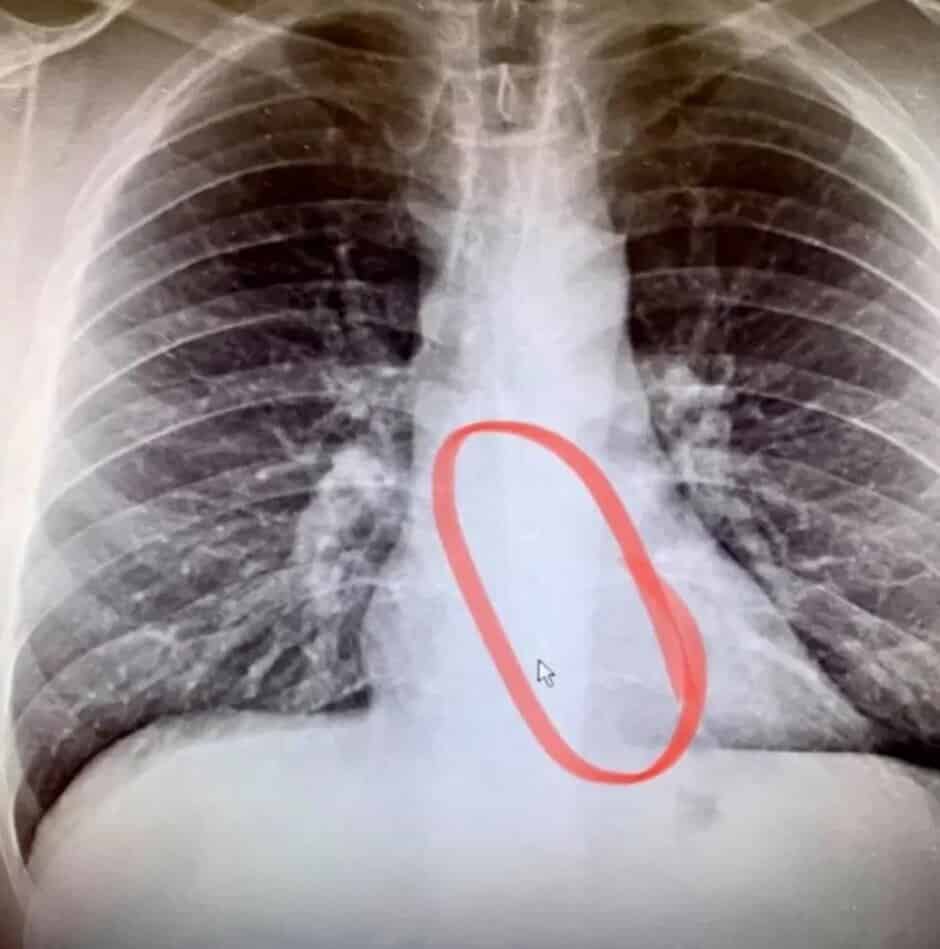

Entretanto ele foi para o hospital. Aí e depois do Raio X percebeu-se que tinha um AirPod preso no esófago. Uma endoscopia de emergência removeu o auricular. A única coisa que aconteceu foi um pequeno desconforto. Bradford admitiu que teve sorte e afirmou que “O médico revelou que é extremamente incomum que um bloqueio não seja doloroso ou extremamente desconfortável. Nunca me ocorreu que dormir com auriculares pudesse ser um risco à segurança. Quanto ao AirPod que ele acidentalmente engoliu continua a funcionar com o áudio perfeito. No entanto, o microfone tem algumas falhas.

Abaixo está uma foto com o auricular removido tirada do Facebook da pessoa que teve de passar por este problema. Continua intacto.